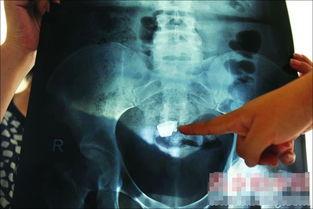

如果找不到怎么办?如果有一根小小的缝针,或者一块纱布等等,数目不对,找不到了怎么办?还有备用方案,因为缝针是金属的,在X线下会显影,术中用的纱布也是带显影条的,拍片可以显影。所以,如果找了很久都没有找到,那就需要术中拍片子帮助寻找,拍片子之后,如果确定异物在患者体内,那就可以有的放矢,帮助寻找。还有的医院,有金属探测器,也可以帮助寻找。

我们做外科医生,最怕的事情之一,就是术中有异物残留体内。为了杜绝这样的事情,术中使用的纱布都是带显影条的,如下图所示,蓝色的是显影条,可以在X线下显影,万一纱布进入腹腔,可以通过拍片来寻找。而宏实医院使用的纱布,居然是不含有显影条的纱布,导致患者腹痛的原因一直没有搞清楚。如果使用的是含有显影条的纱布,即使术中遗留在腹腔里面了,术后通过拍X片或者CT,也能够发现肚子里面的纱布,可以早期做手术取出来,就不会导致肠穿孔,肠梗阻,患者更不会死亡。